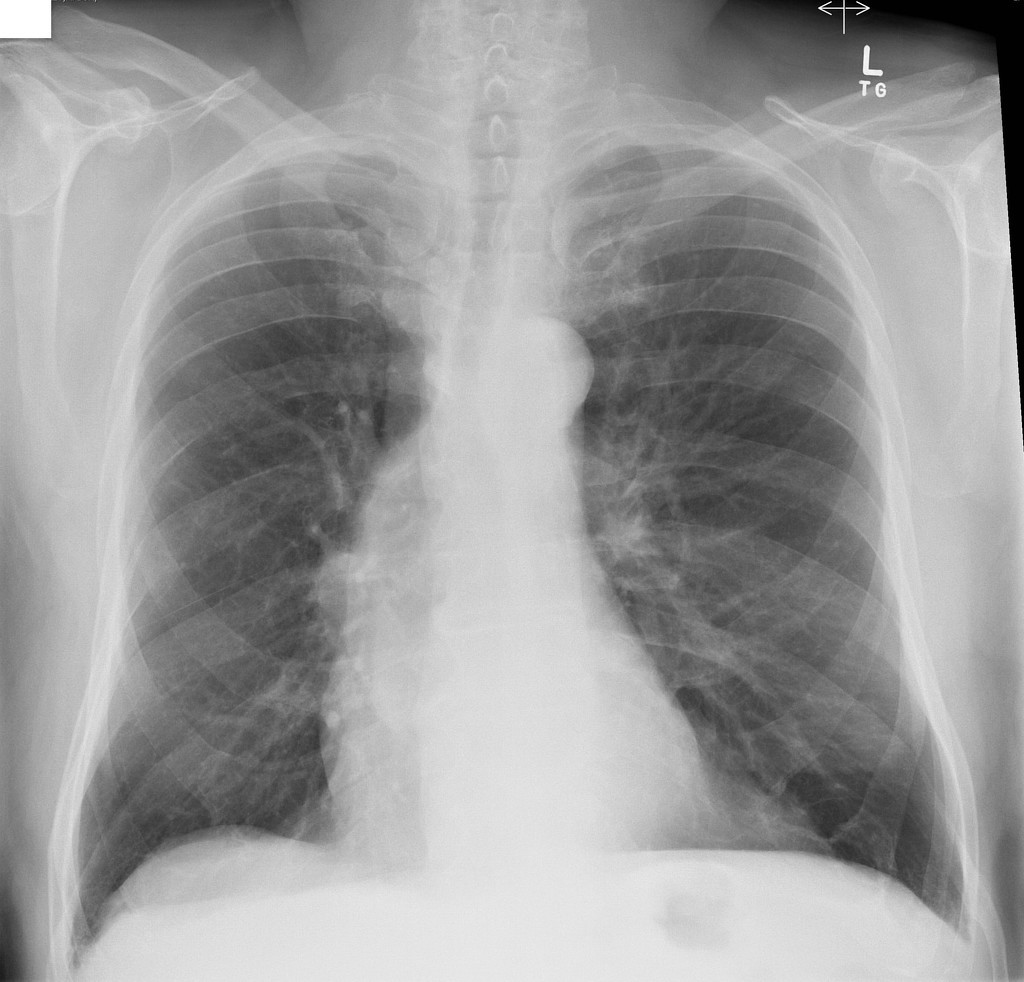

75 ANOS DE IDADE, REFERE DOR TORÁCICA

duplo contorno da borda cardíaca esquerda devido a dilatação da aorta ascendente

ANEURISMA DE AORTA ASCENDENTE